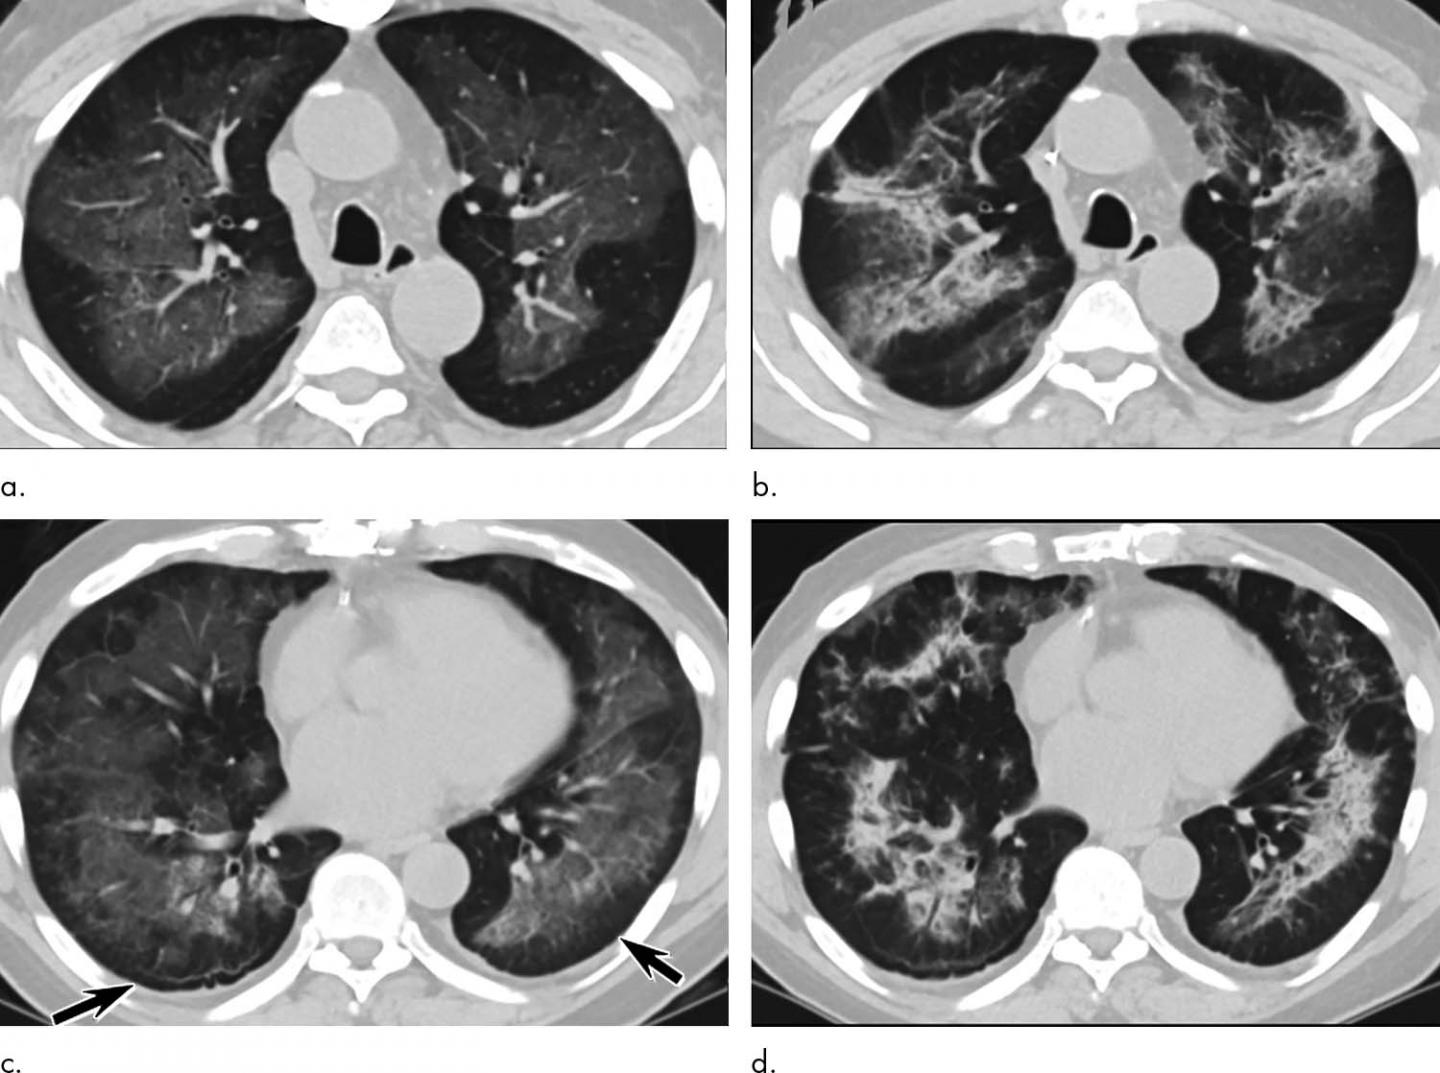

Diseases Free FullText Mosaic Pattern of Lung Attenuation on Chest Popcorn Lung On Ct Bronchiolitis obliterans is also known as obliterative bronchiolitis or constrictive bronchiolitis. On hrct chest, there are often sharply defined, areas of decreased lung attenuation associated with vessels of reduced calibre. Bronchiolitis obliterans) is a rare condition in which lung damage starts in the small airways. Bronchiolitis obliterans (bo), also known as obliterative bronchiolitis, constrictive bronchiolitis and popcorn lung, is a. Popcorn Lung On Ct.

Popcorn Lung On Ct . When it occurs after lung. Bronchiolitis obliterans (bo), also known as obliterative bronchiolitis, constrictive bronchiolitis and popcorn lung, is a disease that results in. Bronchiolitis obliterans is also known as obliterative bronchiolitis or constrictive bronchiolitis. They may also use a pulmonary function test. On hrct chest, there are often sharply defined, areas of decreased lung attenuation associated with vessels of reduced calibre. Popcorn lung is a serious and irreversible condition in which the tiny air sacs in the lungs become scarred and constricted,. Bronchiolitis obliterans) is a rare condition in which lung damage starts in the small airways.

On hrct chest, there are often sharply defined, areas of decreased lung attenuation associated with vessels of reduced calibre. They may also use a pulmonary function test. Bronchiolitis obliterans is also known as obliterative bronchiolitis or constrictive bronchiolitis. Bronchiolitis obliterans (bo), also known as obliterative bronchiolitis, constrictive bronchiolitis and popcorn lung, is a disease that results in. When it occurs after lung. Bronchiolitis obliterans) is a rare condition in which lung damage starts in the small airways. Popcorn lung is a serious and irreversible condition in which the tiny air sacs in the lungs become scarred and constricted,.